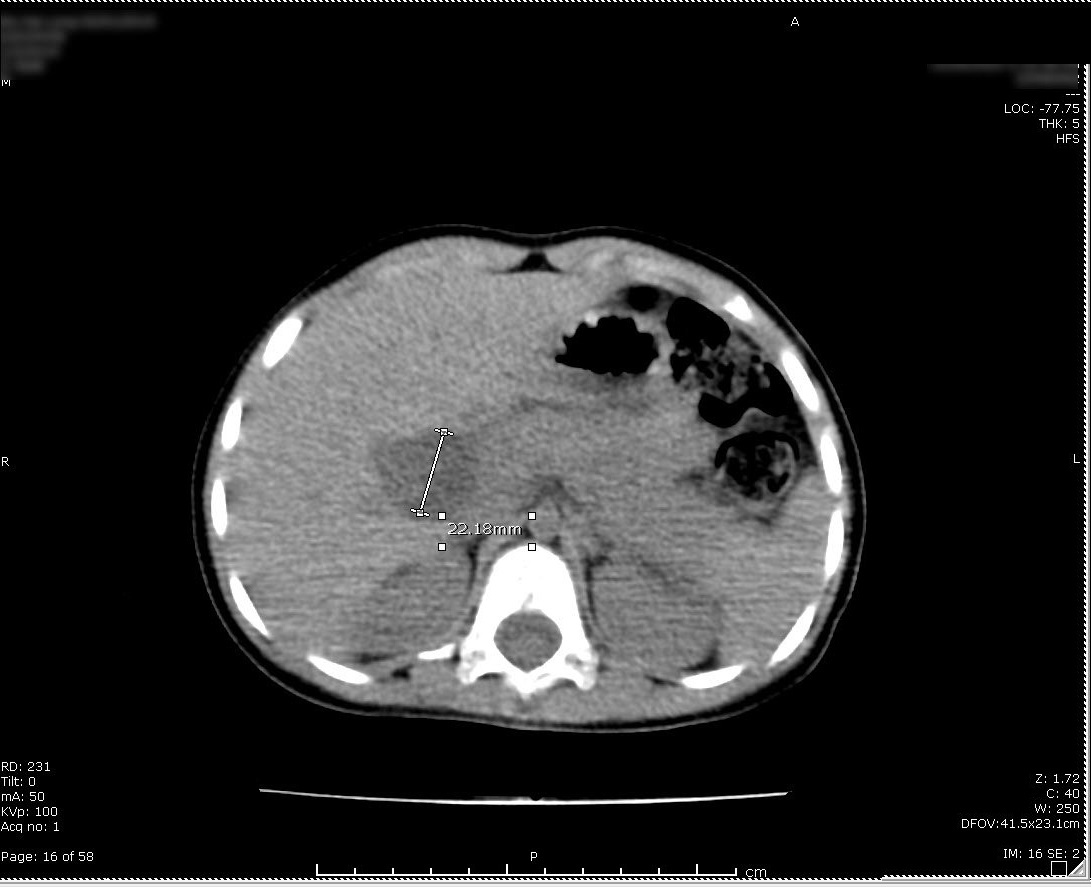

Bệnh nhi nhập viện trong tình trạng đau bụng từng cơn, kèm theo nôn nhiều và có tiền sử viêm tụy cấp nhiều lần. Các kết quả siêu âm và chụp cắt lớp vi tính ổ bụng có thuốc cản quang cho thấy ống mật chủ giãn toàn bộ thành nang đường kính chỗ rộng nhất hơn 20 mm, đến sau đầu tụy.

Kết quả siêu âm của bệnh nhi. Ảnh: BVCC.